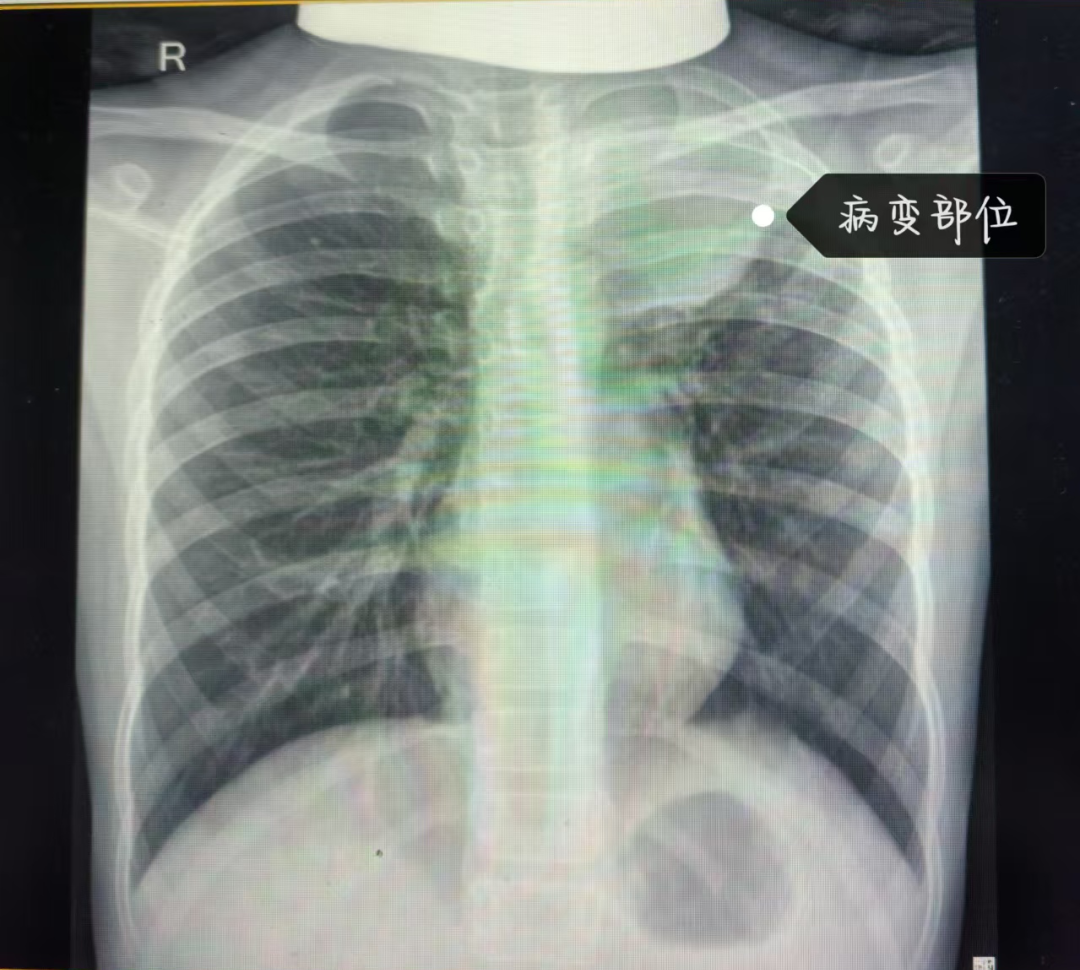

据悉,患儿因高热不退、咳嗽加重来院,经肺部影像学检查提示左肺上叶大面积实变、胸膜增厚,以“重症肺炎”收入儿一科病房。杨俊波副主任为患儿查体,分析其肺部炎症灶实变明显,影响呼吸功能,向家长详细讲明病情后,经同意,于11月5日在全麻下为患儿行纤维支气管镜检查+介入治疗。术中,杨主任精准操作探查支气管病变部位病因,发现患儿左上肺上支完全被白色纤维状痰栓堵塞、开口消失,正是这些内生性异物凝聚成块堵塞了患儿的支气管,致使其无法正常呼吸,危及生命。

以上为取出的树枝状“塑型”痰栓